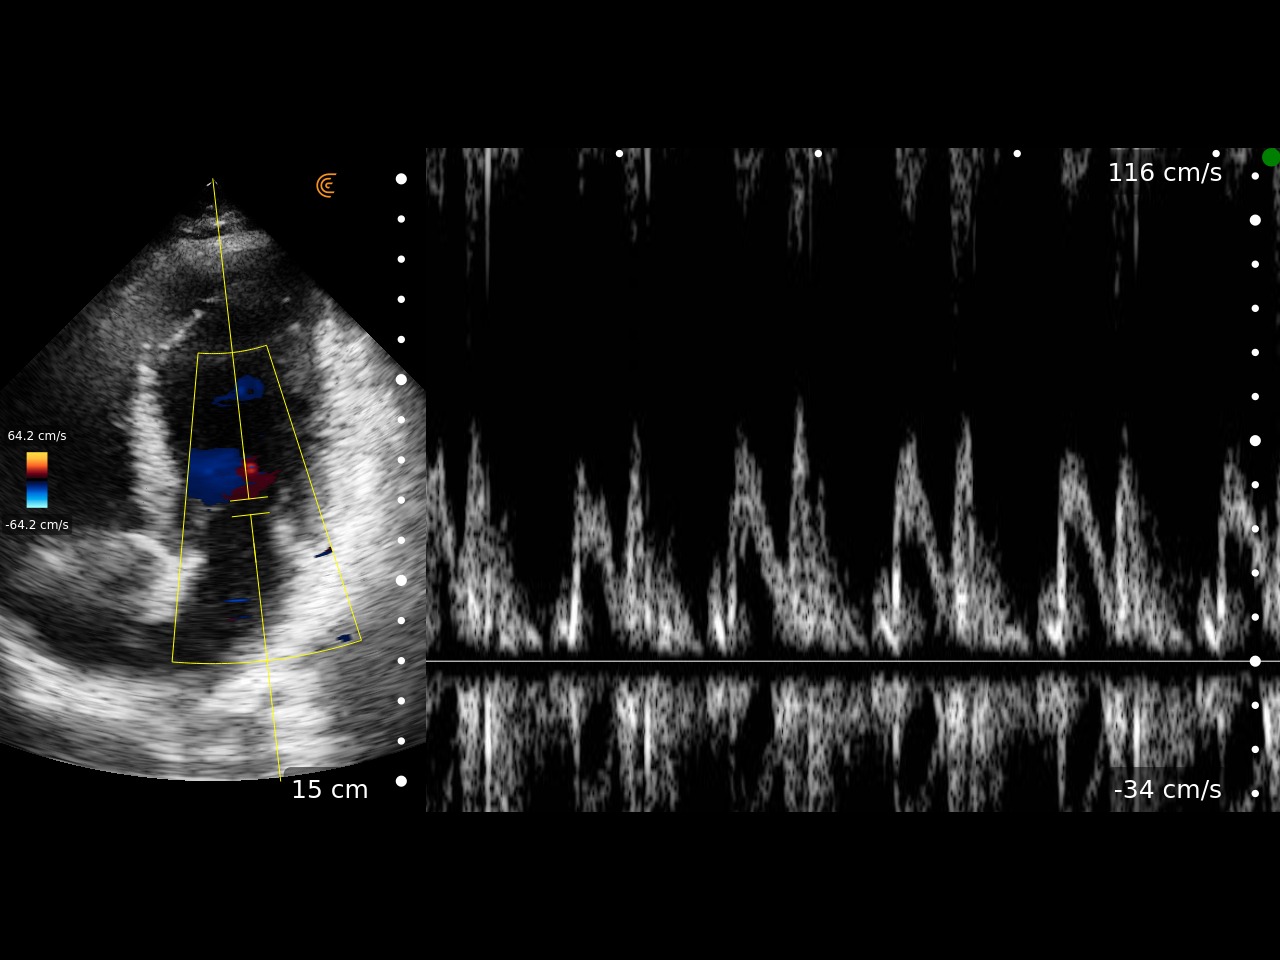

Singurul ecograf wireless de buzunar care oferă o imagine nealterată, comparabilă cu sistemele tradiționale de top. Utilizează o rețea securizată WifiDirect pentru conexiunea cu aplicația de pe multiple dispozitive de vizualizare simultan.

Sondă phased array cu domeniul de frecvență între 1-5 Mhz, adâncimea de scanare reglabilă între 3-40 cm. Moduri de lucru disponibile: B, M, PW, CDFI și Power Doppler. Pachete de măsurători incluse: Cardiac, Abdomen, OB/GYN, Vezică, Plămân, Superficial.

IDEAL PENTRU: Acces abdominal, cardiac, pulmonar, vascular

- Imagini de calitate superioara, comparative cu cele de pe ecografele stationare avansate